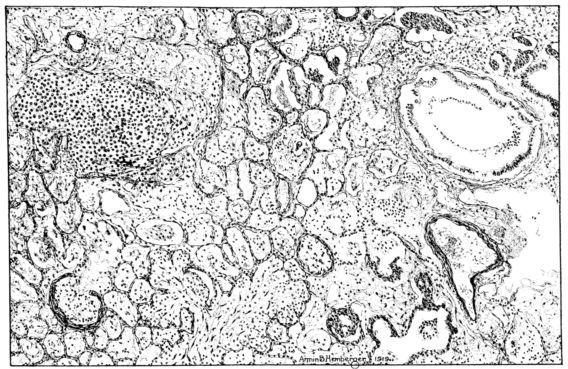

FIG. III. AUTOPSY NO. 90. DRAWING FROM A LESION OF THE TRACHEA (SOMEWHAT OLDER THAN THAT ILLUSTRATED IN FIGURE II). THE MUCOSA IS ENTIRELY LACKING. CONGESTION AND EDEMA ARE THE STRIKING FEATURES IN THE SUBMUCOSA. THE NECROTIZING PROCESS HAS EXTENDED INTO THE MUCUS GLANDS. THIS IS SHOWN IN THE LOWER PICTURE.

The changes are less marked, perhaps, in the trachea than in its finer ramifications. The mucosa is constantly more or less destroyed and large areas, usually focal, are entirely devoid of their epithelial covering. This is replaced by a sparse exudate, composed largely of red blood cells, mucus, a small amount of fibrin, and nuclear fragments (Fig. II). It may dip into the submucosa for a short distance, but usually these indentures are associated with the ducts of the mucous glands into which the inflammatory reaction extends. A more striking feature than the exudate, however, is the edema and the congestion of the submucosa. The loose areolar tissue of the submucosa is spread widely apart, and throughout it distended blood vessels are very conspicuous. Occasionally such a vessel is broken and actual hemorrhage appears in the submucosa. Occasionally, too, the inflammation extends down the duct to the mucous gland itself, and here, also, aplastic inflammatory reaction is evident, inasmuch as the acini now stain intensely red with the cells undifferentiated from each other and specked here and there by broken remains of the dead nuclei (Fig. III). After the disease has continued for a short period, even at the end of five or six days, some regeneration of the epithelial lining may be seen (3) (Fig. IV). But despite this, the acute picture persists, and there goes on, side by side, an attempted repair characterized by epithelial regeneration and the same evidence of acute change. Since the lesion is essentially a superficial one, scars or contractures of any extent are not encountered in the trachea, even in examples of the disease that have ended fatally only after many weeks.[4]

15There is considerable evidence to support the view that the disease spreads from bronchus to bronchus, and in keeping with this view, various stages in the inflammatory processes are more readily determined in these smaller structures than in the trachea. Furthermore, it must be emphasized that even the mildest and the most extreme of these stages are not infrequently encountered in the same lung. The earliest lesion is manifested by an increased homogeneity of the protoplasm of the epithelial lining of the bronchus. The cell protoplasm loses its normal granulation and the nucleus, somewhat darker than usual, becomes conspicuous on a red base (Fig. V). In the lumen of such a tube a serous exudate, perhaps mixed with mucus, is encountered, and there is some spreading apart of the surrounding muscular tissue with engorgement of the vessels. This picture merges gradually into one where the epithelium appears as a homogeneous, red-staining ribbon, devoid of nuclei, often exfoliated, in part at least, from the underlying submucosa (92). The change is traceable through the larger bronchi, even to the ducti alveolares, and not infrequently, bacteria, either as a diffuse, minute dotting or in the form of circumscribed, colony-like formations, are spread through the red, ribbon-like strand (Fig. XVI). With the exfoliation of the epithelial lining, the submucous vessels become more and more conspicuous and may bulge into the lumen of the tube (Fig. VI). That they actually weep into the lumen is proved by the presence of red blood cells in the exudate, now rich in mucus, broken-down nuclei, and desquamated cells. The necrotizing process may not extend deeper than the epithelial lining as is the status described above (140, 162), but it also frequently involves the underlying submucous and muscular layers, so that these lose their identity and stand out as homogeneous masses, in which fragmented nuclei and bacterial accumulations are prominent. Such deeper necrotizing areas may be focal (Fig. VII), or may involve the entire circumference of the tube (Fig. VIII). Occasionally, the epithelium, now dead and staining homogeneously, is lifted from the underlying submucosa in the form of a blister (66), and has very much the same appearance as the well known, early reaction which follows the application of croton oil to the rabbit’s ear. Where this occurs, the submucosa is less involved, as though the necrotizing agent had not penetrated to the same depth and the serous reaction beneath were actually a beneficent exudate. These blisters are in contrast with the deeper areas where the fibrinous mass, mixed with the dead tissue, forms an intensely staining ring or band, which extends through the bronchiolar wall even to the surrounding alveoli.